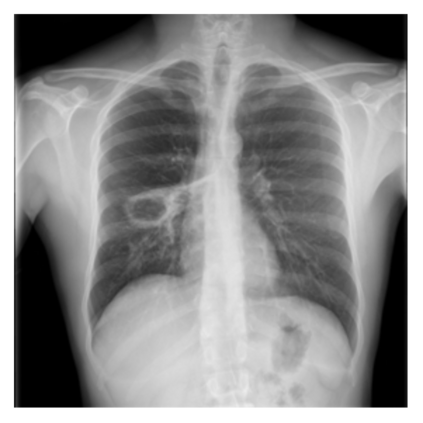

The evaluation of infectious disease processes on radiologic images is an important and challenging task in medical image analysis. Pulmonary infections can often be best imaged and evaluated through computed tomography (CT) scans, which are often not available in low-resource environments and difficult to obtain for critically ill patients. On the other hand, X-ray, a different type of imaging procedure, is inexpensive, often available at the bedside and more widely available, but offers a simpler, two dimensional image. We show that by relying on a model that learns to generate CT images from X-rays synthetically, we can improve the automatic disease classification accuracy and provide clinicians with a different look at the pulmonary disease process. Specifically, we investigate Tuberculosis (TB), a deadly bacterial infectious disease that predominantly affects the lungs, but also other organ systems. We show that relying on synthetically generated CT improves TB identification by 7.50% and distinguishes TB properties up to 12.16% better than the X-ray baseline.